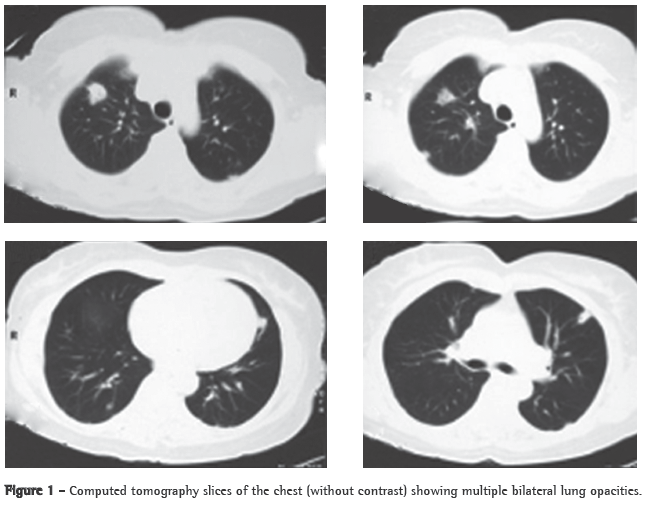

A 56-year-old Caucasian female sought treatment in the emergency room presenting a painful, right-sided neck tumor for 5 days. The patient reported a dry cough and high fever for 3 days. She described herself as a nonsmoker. She was hypertensive and diabetic. She had experienced a myocardial infarction 3 years prior. At admission, the patient was dehydrated and afebrile (axillary temperature, 36.7°C). She presented normal respiration. Laboratory tests revealed increased erythrocyte sedimentation rate (92 mm). Ultrasound of the neck showed IJV thrombosis, and anticoagulation was started on post-admission day 4. A chest X-ray demonstrated at least two nodules in the left lung, one apparently cavitated and one with a diameter of 18 mm at its base, as well as an irregular lesion, 25 mm in diameter, in the right upper lung lobe. A transesophageal echocardiogram, performed in order to rule out endocarditis, demonstrated no vegetation. Due to the hypothesis of pneumonia, empirical treatment with oral cefuroxime (500 mg every 12 h) was started. A computed tomography scan of the chest revealed multiple bilateral lung opacities, with an aspect suggestive of metastatic implants (Figure 1). The patient was then submitted to fiberoptic bronchoscopy, the findings of which were normal. In the microbiological analysis of the bronchoalveolar lavage fluid, testing for acid-fast bacilli and fungi were negative, as were the cytopathologic study and cultures. Since the working diagnosis was metastatic neoplasm, the patient underwent surgical lung biopsy. The anatomopathological examination of the sample showed chronic suppurative inflammation with organizing abscesses in lung parenchyma. In view of the hypothesis of Lemierre's syndrome caused by jugular thrombosis accompanied by septic pulmonary embolism, the patient was questioned regarding the occurrence of tonsillitis at the onset of the disease. The patient had no recollection, but her daughter remembered that the patient had used oral amoxicillin (500 mg every 8 h for 10 days) for the treatment of tonsillitis some days prior to hospitalization. At hospital admission, the patient received a course of intravenous cefuroxime (750 mg every 8 h for 7 days) concomitantly with oral azithromycin (500 mg once a day for 5 days). Subsequently, because fever persisted, she was treated with cefepime (1,000 mg every 12 h for 7 days). A control computed tomography scan of the chest performed after this course of antibiotics showed nearly complete resolution of the opacities (Figure 2). The patient had been afebrile since the third day of the new course of antibiotics. No microorganisms were isolated from blood cultures or bronchoalveolar lavage cultures. Since there is no evidence that it is beneficial in cases of Lemierre's syndrome, anticoagulation was discontinued after 20 days.

The response to antibiotics is slow. The mean time between the initiation of treatment and the resolution of fever ranges from 8 to 12 days.

Fusobacterium sp. is generally sensitive to penicillin, clindamycin, metronidazole, cephalosporins, tetracycline and chloramphenicol. The initial regimen suggested is penicillin and metronidazole for at least two weeks. In cases of penicillin treatment failure, the options are ticarcillin/clavulanate and imipenem In the case reported here, amoxicillin, cefuroxime, cefepime and azithromycin were used. The patient became afebrile only after the third antibiotic regimen, which might be due to the short duration of antibiotic use, rather than to antibiotic treatment failure.